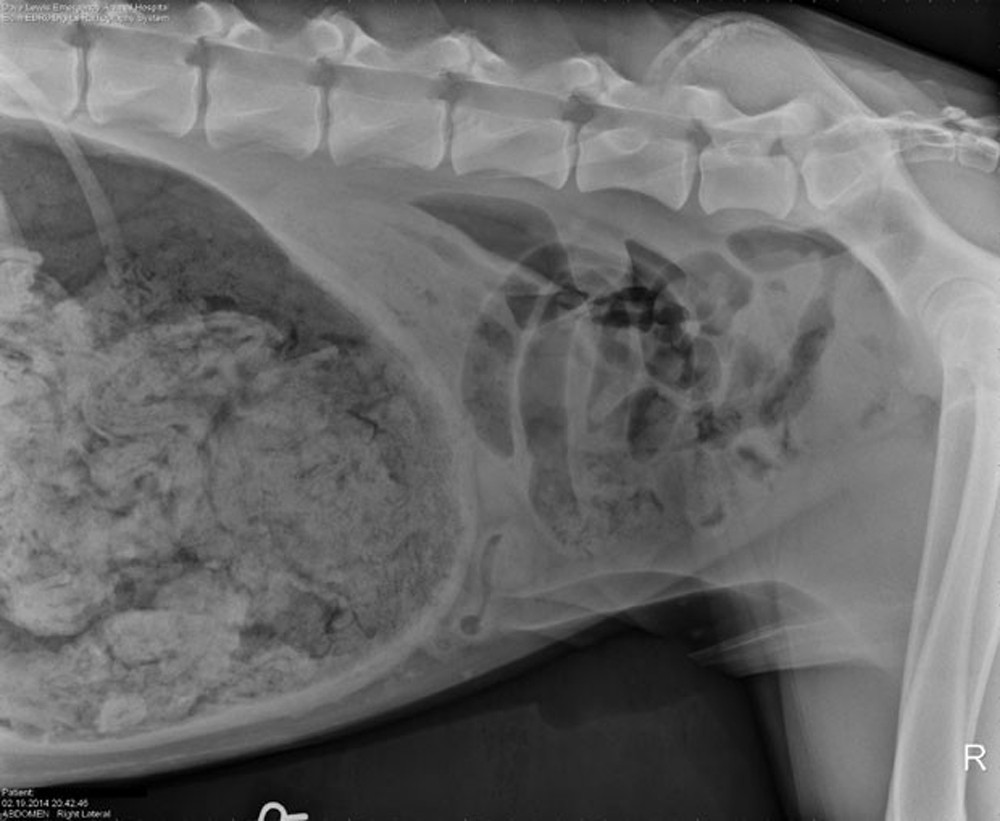

Caso ocorreu em Portland, no Oregon, | Foto: Reprodução

Um exame de raio-X acabou revelando o que vinha provocando as dores no animal. O raio-X mostrou uma grande "quantidade de material estranho" no estômago do cão.

O raio-X rendeu à clínica um prémio US$ 500 em um concurso promovido pela revista "The Veterinary Practice News", que elegeu as imagens mais bizarras de objetos comidos por animais de estimação.